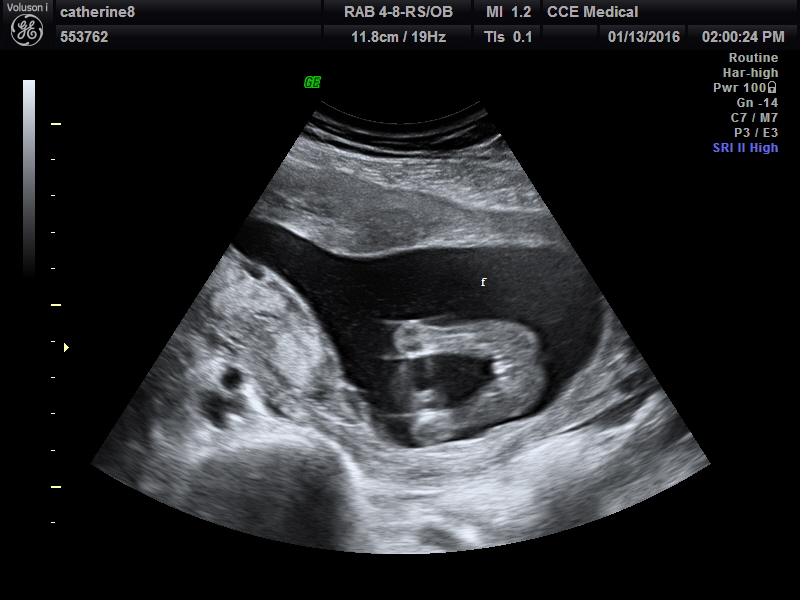

Attachment 29319Attachment 29320Attachment 29321Attachment 29322

Snuck to a private scan at 16 weeks 3 days. No chance in gender changing right??